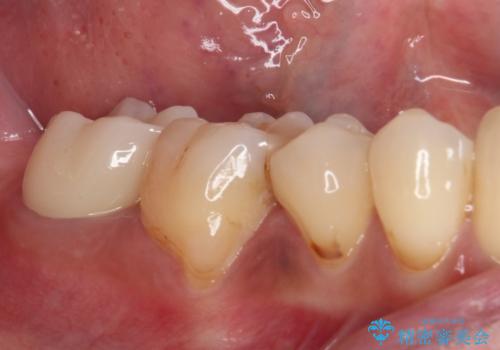

左右の臼歯は、当初1歯対1歯の咬合でしたが、終了時には理想とされる1歯対2歯に改善させることができました。

治療途中ではオープンバイトになってしまう局面もあるほど、患者様の気になっていたディープバイトをしっかりと改善することができました。

ディープバイトの改善により就寝中の食いしばりも改善され、患者様には大変満足していただきました。